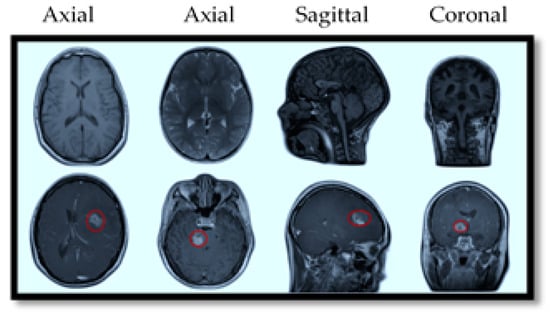

Multi-view imaging: MRI captures images in multiple planes (axial, coronal, and sagittal), providing a comprehensive view of a tumor’s size, shape, location, and relationship to nearby structures. This is crucial for effective surgical planning and treatment decisions.

MRI also offers specialized imaging sequences that provide valuable insights into brain tumors, such as diffusion-weighted imaging (DWI), which helps differentiate tumor cells from healthy brain tissue; perfusion imaging, which assesses blood flow within the tumor to evaluate its aggressiveness; and magnetic resonance spectroscopy (MRS), which analyzes the tumor’s chemical composition to aid in diagnosis and treatment planning. For illustration purposes, Figure 2 provides a visual comparison of normal and tumorous brain MRI images with encircled areas, and Figure 3 illustrates the types of brain tumors in MRI images.

MRI scans are typically obtained in three anatomical planes—axial, coronal, and sagittal—each offering distinct views of brain structures and abnormalities, illustrated in Figure 2. Utilizing data specific to these planes in brain tumor detection and classification models allows for a comprehensive understanding of tumor characteristics. These MRI view-specific models capitalize on the strengths inherent to each anatomical plane, enhancing diagnostic precision and accuracy. Figure 3 shows these multiple-view MRI slices and brain tumor classifications.